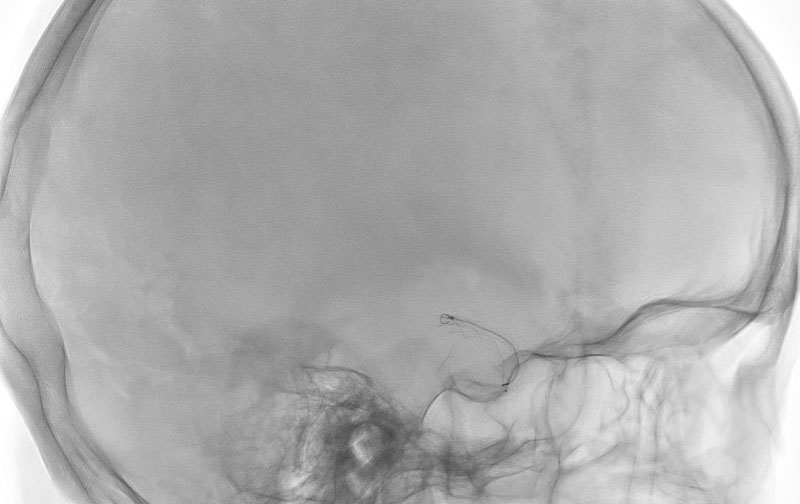

No.1595 手術中